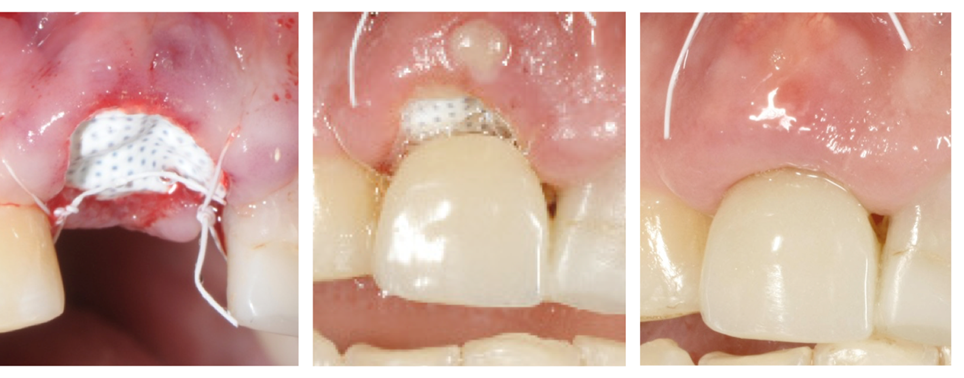

La membrana viene ulteriormente stabilizzata usando una sutura incrociata in PTFE Cytoplast®. In alternativa si possono posizionare dei punti interrotti. Le suture in PTFE, che causano una risposta infiammatoria minima, vengono lasciate in sito per 10-14 giorni.

La membrana viene rimossa in modo non chirurgico dopo 3-4 settimane. Gli studi hanno infatti dimostrato che in tale periodo si forma una matrice di tessuto connettivo denso e vascolarizzato e una prima osteogenesi viene osservata nei 2/3 della cavità.

Dopo 6 settimane la gengiva cheratinizzata ha iniziato a formarsi sopra la cavità che è stata riempita. La naturale architettura del tessuto molle è preservata, incluso la papilla interdentale.

Tre momenti: al momento della chirurgia, dopo 1 settimana e dopo 4 settimane

Immagine clinica e radiografica al momento della rimozione della membrana